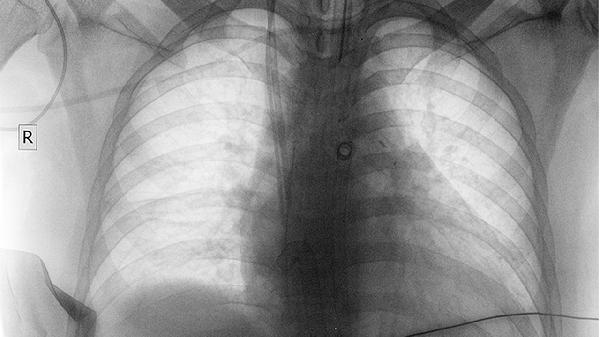

2、症状感知的滞后性

年轻肺组织代偿能力强,等出现明显咳嗽、胸痛时,通常已错过最佳干预时机。建议每年做一次低剂量CT筛查。